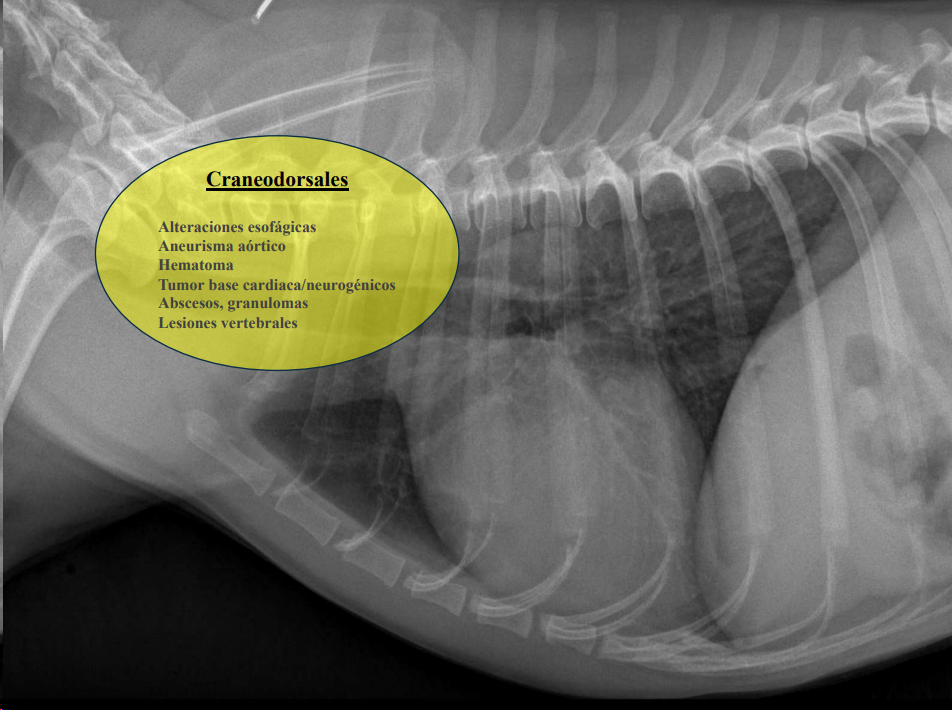

CLASIFICACIÓN DE MASAS MEDIASTÍNICAS

-

Craneodorsales: alteraciones esofágicas, aneurisma aórtico, hematoma, tumor base cardíaca/neurogénico, absceso, granuloma, lesión vertebral.

Desplazamiento traqueal ventral por neumoesofago

Desplazamiento traqueal dorsal por masa en el mediastino craneal